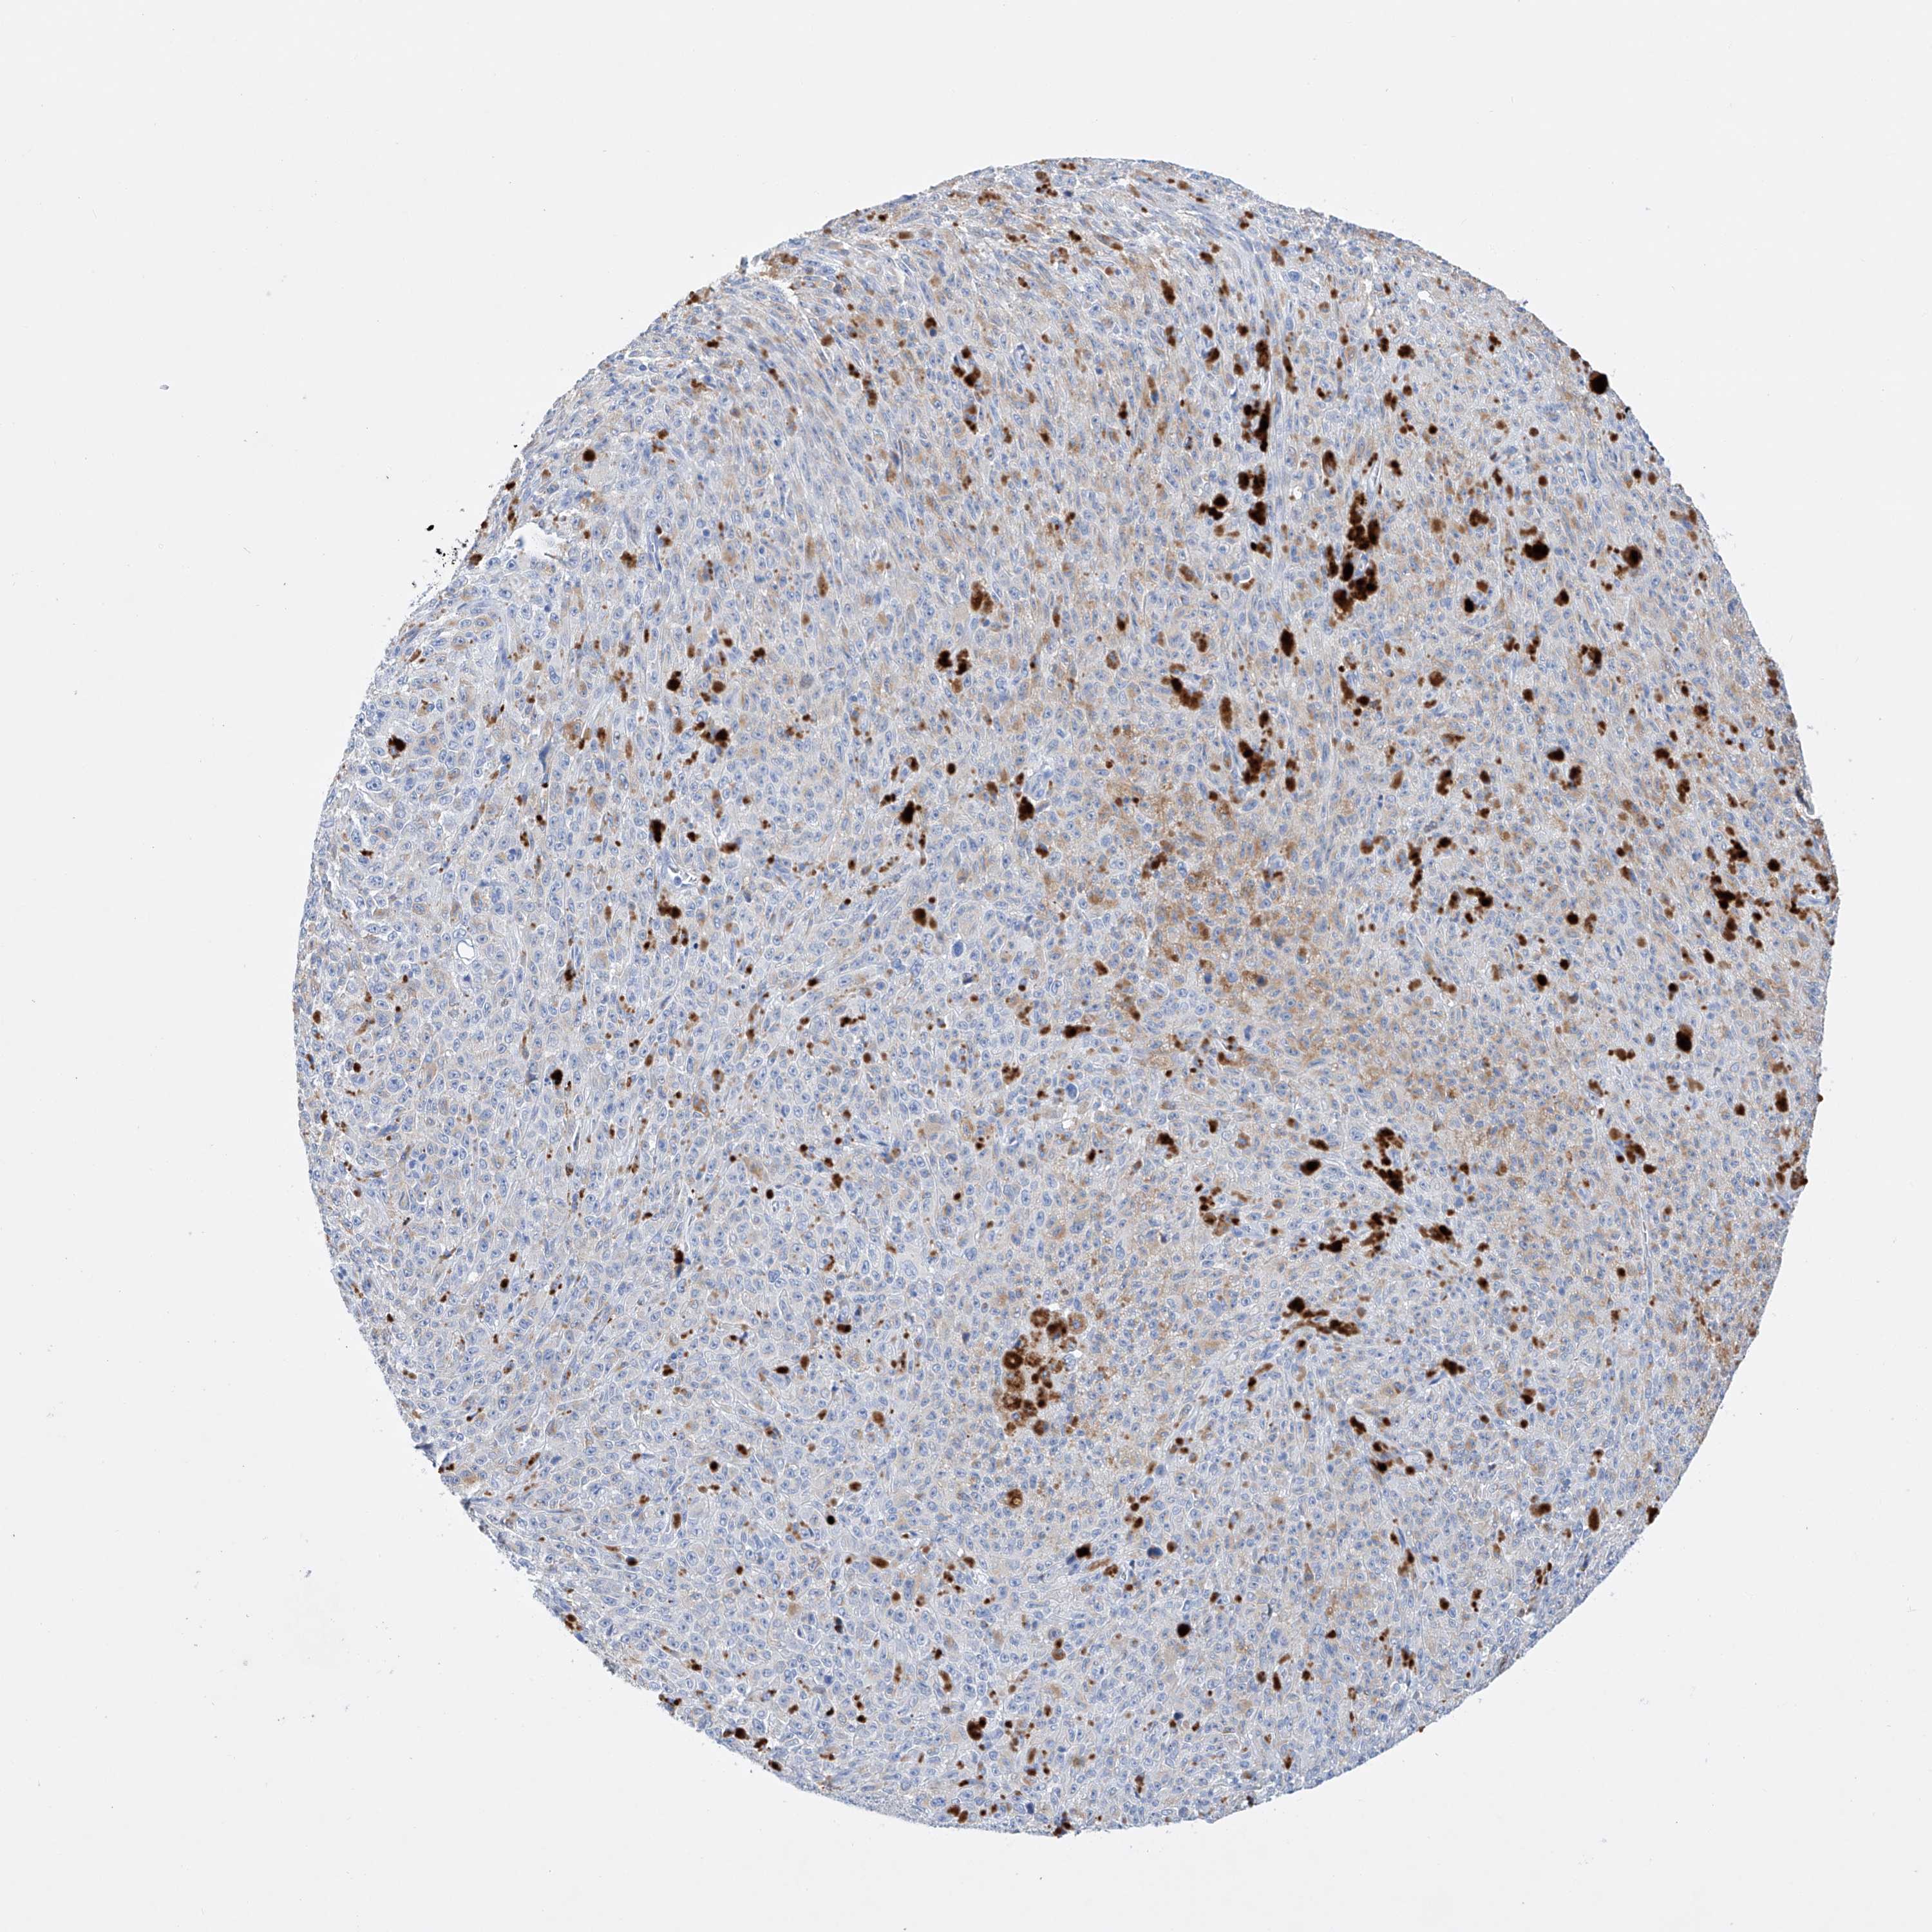

MELANOMA - Protein expressioni

A mouse-over function shows sample information and annotation data. Click on an image to view it in a full screen mode. Samples can be filtered based on level of antibody staining by selecting one or several of the following categories: high, medium, low and not detected. The assay and annotation is described here.

Note that samples used for immunohistochemistry by the Human Protein Atlas do not correspond to samples in the TCGA dataset.

Antibody stainingi

Antibody staining in the annotated cell types in the current human tissue is reported as not detected, low, medium, or high, based on conventional immunohistochemistry profiling in selected tissues. This score is based on the combination of the staining intensity and fraction of stained cells.

Each image is clickable and will lead to virtual microscopy that enables deeper exploration of all samples and also displays staining intensity scores, fraction scores and subcellular localization as well as patient and tissue information for each sample.

Antibody HPA030060

Antibody HPA030061

Staining

High

Medium

Low

Not detected

Intensity

Strong

Moderate

Weak

Negative

Quantity

>75%

75%-25%

<25%

None

Location

Nuclear

Cytoplasmic/membranous

Cytoplasmic/membranous,nuclear

Malignant melanoma, NOS

Malignant melanoma, Metastatic site